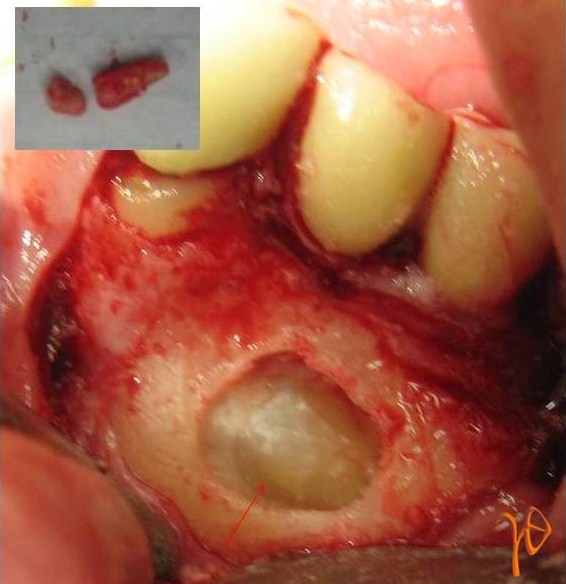

Eικ. 12 : Διεγχειρητική εικόνα του υπεράριθμου προγομφίου της Περίπτωσης-3(βέλος), ο οποίος διχοτομήθηκε για τις ανάγκες της εξαγωγής (ένθετη φωτογραφία).